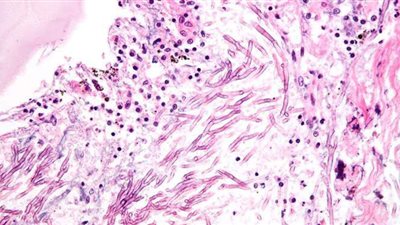

ويتميز هذا المرض بالالتهاب الحاد في الأوعية غير المعروف مصدرها، وتشمل أعراض المرض الحمى والطفح الجلدي والتهاب العينين واحمرارًا في البلعوم وتجويف الفم، وتورمًا في أكف اليدين والقدمين وتضخم العقد اللمفاوية في الرقبة.

وبحسب موقع "مايو كلينك" يطلق على داء كاواساكي أحيانًا متلازمة العُقَد اللمفية المخاطية؛ لأنه يُصيب أيضًا الغدد التي تنتفخ أثناء العدوى (العُقَد اللمفية) والجلد والأغشية المخاطية داخل الفم والأنف والحنجرة.

وبالإضافة إلى ذلك، فإن داء كاواساكي يؤدي إلى تطور (نشوء) التهاب السَّحايا (التهاب الغشاء الذي يغطي الدماغ والنخاع الشوكي).